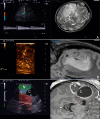

Introduction: Glioma surgery is aimed at obtaining maximal safe tumor resection while preserving or improving patient's neurological status. For this reason, there is growing interest for intra-operative imaging in neuro-oncological surgery. Intra-operative ultrasound (ioUS) provides the surgeon with real-time, anatomical and functional information. Despite this, in neurosurgery ioUS mainly relies only on gray-scale brightness mode (B-mode). Many other ultrasound imaging modalities, such as Fusion Imaging with pre-operative acquired magnetic resonance imaging (MRI), Doppler modes, Contrast Enhanced Ultrasound (CEUS), and elastosonography have been developed and have been extensively used in other organs. Although these modalities offer valuable real-time intra-operative information, so far their usage during neurosurgical procedures is still limited. Purpose: To present an US-based multimodal approach for image-guidance in glioma surgery, highlighting the different features of advanced US modalities: fusion imaging with pre-operative acquired MRI for Virtual Navigation, B-mode, Doppler (power-, color-, spectral-), CEUS, and elastosonography. Methods: We describe, in a step-by-step fashion, the applications of the most relevant advanced US modalities during different stages of surgery and their implications for surgical decision-making. Each US modality is illustrated from a technical standpoint and its application during glioma surgery is discussed. Results: B-mode offers dynamic morphological information, which can be further implemented with fusion imaging to improve image understanding and orientation. Doppler imaging permits to evaluate anatomy and function of the vascular tree. CEUS allows to perform a real-time angiosonography, providing valuable information in regards of parenchyma and tumor vascularization and perfusion. This facilitates tumor detection and surgical strategy, also allowing to characterize tumor grade and to identify residual tumor. Elastosonography is a promising tool able to better define tumor margins, parenchymal infiltration, tumor consistency and permitting differentiation of high grade and low grade lesions. Conclusions: Multimodal ioUS represents a valuable tool for glioma surgery being highly informative, rapid, repeatable, and real-time. It is able to differentiate low grade from high grade tumors and to provide the surgeon with relevant information for surgical decision-making. ioUS could be integrated with other intra-operative imaging and functional approaches in a synergistic manner to offer the best image guidance for each patient.